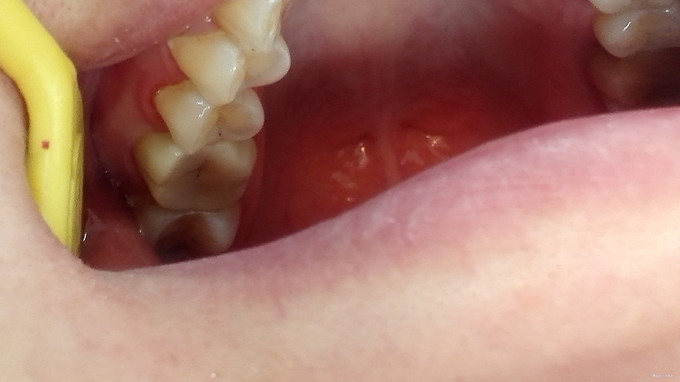

检查:16牙合面暂封完好,咬合紧,牙合龈距离<5mm,叩痛(-),牙体无松动,牙龈未见异常 X线示:16已根治,根充良好,根充物恰到根尖孔,根尖及牙周未见异常

诊断:16牙体缺损 治疗计划:16嵌体冠修复 治疗:1.取局部印模,制备髓腔固位形,预备牙体,取模,比色:A3, 寄送加工厂,制备临时冠,试戴,调合,磨光,粘固临时冠 2.主诉:戴牙 检查:16临时冠完好,叩痛(—),牙体无松动,牙龈未见异常 处置:戴入16全瓷嵌体冠,调节使就位顺利,与基牙密贴,冠边缘伸张合适,邻接恢复良好,调牙合,抛光,患者满意,U200粘固,嘱须知

随着牙髓治疗技术的发展与完善,经过完善治疗的残冠、残根得以长期保留,常用的方法是桩核冠修复,但是对于牙合龈距离过低的磨牙牙冠修复的固位问题一直是临床修复医生的一大困扰。通过采用在牙体预备时使轴壁相互平行,减少牙体预备时的锥度来增加固位力的方法效果不显著。而嵌体冠具备嵌体、全冠两者的结构特点,既可以从冠内也可以从冠外获得固位力,从而取得良好的修复效果。它适用于咬合紧,牙合龈距离短(<5mm),经牙髓治疗的死髓牙。 本病例表现为咬合紧,牙合龈距离短,难以用常规的修复方法完成治疗。经过认真的口腔检查,结合X线牙片,患者的需求,综合分析判断患牙的保留修复价值。牙体预备时,轴壁相互平行,髓腔固位的洞壁无倒凹,微外展,点、线、角清晰,洞缘形成45度洞斜面。 嵌体冠嵌入牙体窝洞内,利用髓腔固位,和基牙轴壁间形成很强的机械嵌合力,同时覆盖牙体外部,和冠边缘形成环抱,内外形成一个大整体,共同构成嵌体冠的抗力系统,有效提高了患牙在行使功能时的抗力,恢复了生理功能和外形。在临床操作中,选择好适应症,再根据牙体形态、牙髓活力、修复体的长度、残余健康牙体组织量等不同来确定嵌体洞型的大小、深度、形状等。